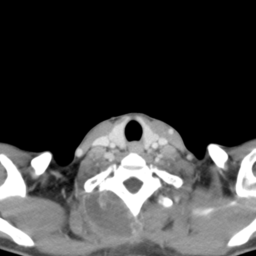

![]() |

| (a) | (b) | (c) | (d) |

Unsupervised Categorization: Our category discovery clusters are generally visually coherent within the cluster and size-balanced across clusters. However, image clusters formed only based on text information (of radiology reports) are highly unbalanced [49], with three clusters inhabiting the majority of images. Note that our method imposes no explicit constraint on the number of instances per cluster. Fig. 6 shows sample images and their top-10 associated key words from two randomly selected clusters (more results are provided in the supplementary material). The LDPO clusters are found to be clinically or semantically related to the corresponding key words, which describe presented anatomies, pathologies (e.g., adenopathy, mass), their associated attributes (e.g., bulky, frontal) and imaging protocols or properties.

The category discovery clusters employing our LDPO method are found to be more visually coherent and cluster-wise balanced in comparison to the results in [49] where clusters are formed only from text information ( radiology reports). Fig. 7 Left shows the image numbers for each cluster from the AlexNet-FC7-Topic setting. The numbers are uniformly distributed with a mean of 778 and standard deviation of 52. Fig. 7 Right illustrates the relation of clustering results derived from image cues or text reports [49]. Note that there is no instance-balance-per-cluster constraints in the LDPO clustering. The clusters in [49] are highly uneven: 3 clusters inhabit the majority of images. Fig. 6 shows sample images and top-10 associated key words from 5 randomly selected clusters (more results in the supplementary material). The LDPO clusters are found to be semantically or clinically related to the corresponding key words, containing the information of (likely appeared) anatomies, pathologies (e.g., adenopathy, mass), their attributes (e.g., bulky, frontal) and imaging protocols or properties.